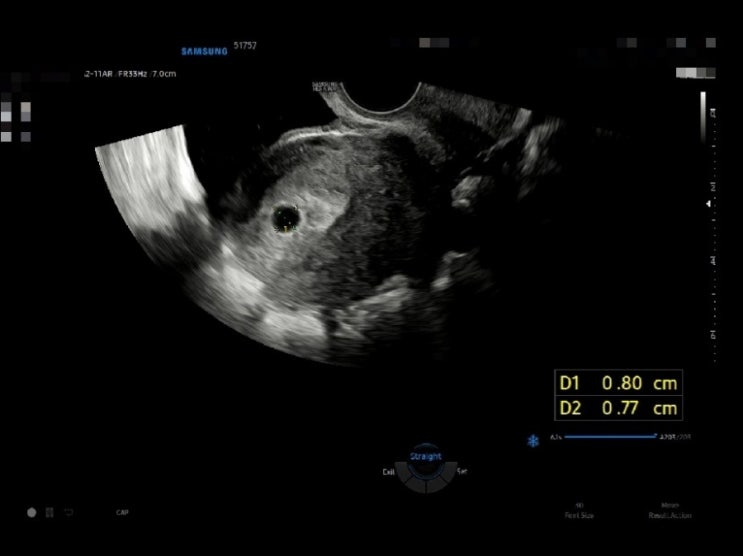

5주차, 아기집 확인&임산부 배지

4주차에 확인하지 못한 아기집을 5주차에 확인했다. 직경 0.8cm의 작고 소중한 아기집 아기집만 보여서 그...